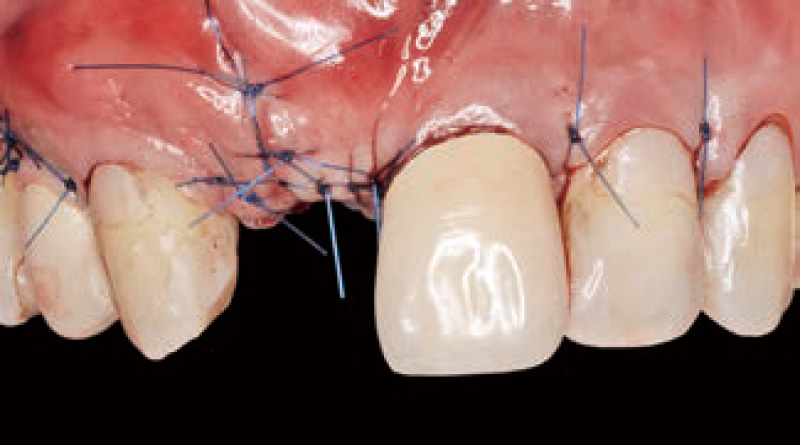

3次元的に補綴主導位置へインプラントフィクスチャーを埋入し(図4)、Tiハニカムメンブレンを口腔外で適切なサイズにトリミングした後、頰側に2カ所ボーンタックでメンブレンを固定。露出しているフィクスチャー周囲に骨移植材を移植し、Tiハニカムメンブレンを口蓋側に向けて湾曲形態を付与し(図5)、5-0ナイロンを用いて単独水平マットレス縫合と単純縫合にて一次閉鎖を行った(図6)。術後2週間で全ての抜糸を行ったが切開線中央部にピンホール上のくぼみを認め、ペリオプローブで触診するとTiハニカムメンブレンがごくわずかに露出し口腔内と交通していた。患者には2週間前にセルフケアチェックとプロケアを7ヵ月間行い、臨床症状も特記事項なく経過した(図7)。

図6 水平マットレスを根尖側、より歯冠側の2ヵ所で縫合し、切開線は単純縫合で閉鎖。![[写真] 術後7ヵ月の創部](/academic/dentalmagazine/wp-content/uploads/sites/2/2021/12/179-17_photo07.jpg)